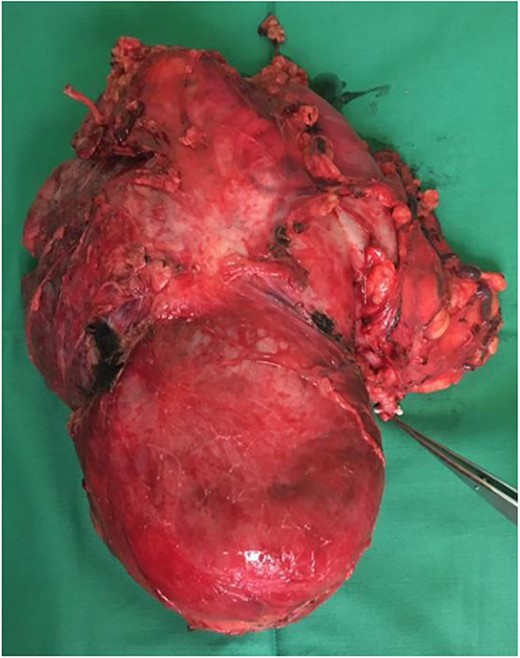

Our initial approach was a midline laparotomy. Upon entering the peritoneum, the huge tumour sized 12 cm × 15 cm was identified. Inferiorly, the overlying transverse mesocolon was noted to be stretched. Laterally, the tumour was densely adherent to the medial aspect of the left kidney, and the left adrenal gland was not visualized due to the extensive involvement of the left kidney (Figs 5 and 6). Posteriorly, the tumour was also adhered to the duodenojejunal junction, spleen and pancreatic tail; however, we managed to shave off and preserve the organs. Intra-operatively, multiple units of transfusion were required. The tumour weighed 1.2 kg.

Intra-operatively, the tumour was stretching the mesocolon, and laterally adherent to the left kidney